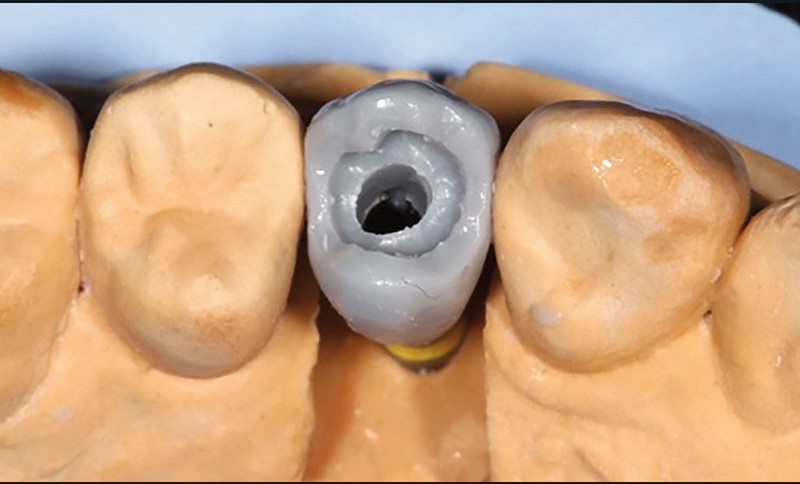

Après la confection des modèles de travail et transfert en articulateur, le prothésiste dentaire choisi l’embase titane (Variobase®, Straumann) correspondante au diamètre implantaire et à la hauteur prothétique disponible. Ces Variobases sont modifiables au laboratoire uniquement si une réduction de hauteur s’impose.

Dans un premier temps, le prothésiste réalise une maquette en cire de la restauration sur l’embase titane (fig. 2).